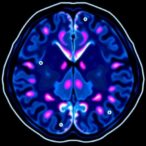

This comprehensive investigation evaluated an extensive cohort of 2,071 urothelial carcinomas from male patients, highlighting the largest tissue microarray analysis focused on this chromosomal anomaly. Among these cases, 487 patients had undergone cystectomy for muscle-invasive disease with available follow-up data, providing a robust framework to gauge the potential clinical significance of LOY. Fluorescence in-situ hybridization (FISH) techniques were employed to detect the presence or absence of the Y chromosome within tumor specimens, ensuring a precise molecular characterization.

One of the study’s pivotal findings concerns the prevalence of LOY across different tumor stages. Overall, 26.0% of 1,704 analyzable cancers exhibited loss of chromosome Y, a frequency that remained surprisingly stable between lower-grade non-invasive carcinomas and more advanced muscle-invasive types. For instance, early-stage pTa G2 and pTa G3 carcinomas had LOY frequencies of approximately 22.8% and 24.1%, respectively, showing no significant statistical difference. Meanwhile, muscle-invasive tumors from pT2 to pT4 stages displayed only a modest increase in LOY incidence, which, critically, did not reach significance.

Crucially, the investigation extended its scope to the tumor microenvironment, a complex and dynamic ecosystem known to influence cancer growth, immune evasion, and therapeutic response. Using detailed immunophenotypic data from a prior study, the researchers assessed whether LOY status corresponded to variations in immune cell infiltrates, including cytotoxic CD8+ T lymphocytes, macrophages, dendritic cells, and subsets of helper and regulatory T cells. Strikingly, no significant differences emerged between tumors harboring LOY and those retaining the Y chromosome, suggesting that LOY does not substantially alter the immune landscape in muscle-invasive urothelial carcinomas.